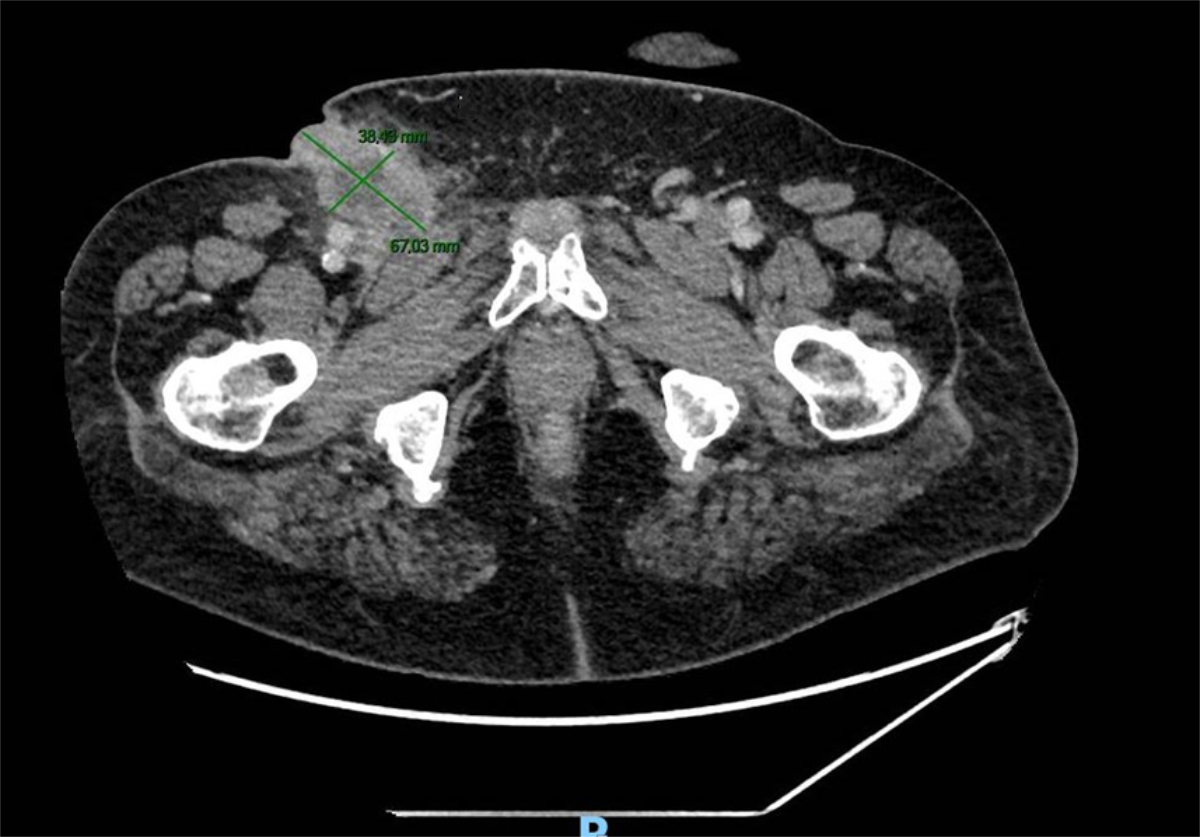

A 70-year-old patient presented to an emergency department with a history of a painful mass in the right groin. After 1 month, the pain increased, and the patient experienced a local abscess and fistulization. There were no previous problems with the ipsilateral lower limb or any associated fever or rash symptoms. His past medical history included anticoagulant therapy for atrial fibrillation, psoriasis (lower abdominal region, both groins and scrotum) and a squamous cell carcinoma on the prepuce with local surgery a year before (T1, N0, M0, R0). The 3 × 8 cm inguinal mass was drained under local anaesthesia, followed by oral antibiotic therapy for 10 days. An ultrasound-guided biopsy was performed without any clear histological findings. Because of a worsening of the local status and a possible relationship with the prepuce squamous cell carcinoma, a new examination of the glans revealed local recurrence. A computed tomography (CT) scan showed multiple bilateral groin lymphadenopathies with an abcess on the right side (figure 2). Another biopsy confirmed metastasis of the penile squamous cell carcinoma. After a multidisciplinary tumour board discussion, a radical lymph node dissection was performed, which showed 13/15 positive superficial (inguinal) nodes and 3/10 positive deep (iliac) nodes. The postoperative course was complicated by lymphatic fistula and wound infection. Immunotherapy (durvalumab and nivolumab) was later introduced, but the patient died after 7 months of multisystemic complications.

Figure 2CT imaging showing the ulcerated right-groin lymphadenopathy.